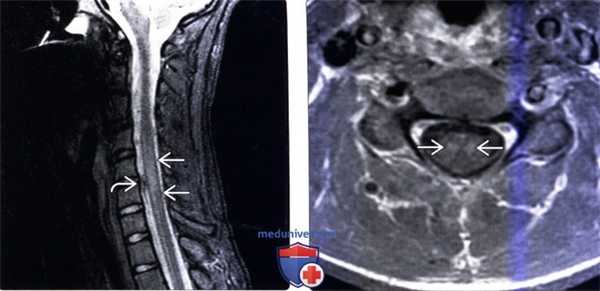

(Слева) Сагиттальный срез, STIR МР-И: патологическое увеличение объема и отек среднешейного отдела спинного мозга на протяжении трех позвоночных сегментов. Участок низкой интенсивности сигнала СМЖ вдоль вентральной поверхности спинного мозга представляет собой артефакт пульсации СМЖ.

(Справа) Аксиальный срез Т1-ВИ с КУ (этот же пациент) отмечается патологическое двустороннее контрастное усиление сигнала центральных отделов паренхимы на фоне патологического увеличения объема шейного отдела спинного мозга.